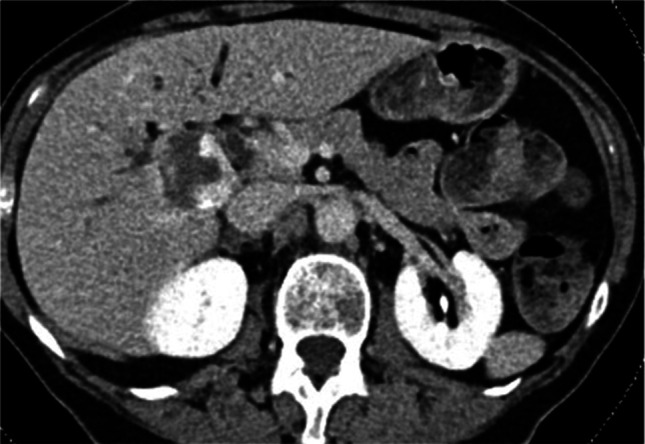

Symptomatic hepatic hemangiomas are commonly treated by transcatheter arterial embolization as an alternative to surgical resection. Bile duct complications are rare. An 80-year-old woman had a progressive refractory stricture postbleomycin transcatheter arterial chemoembolization. Magnetic resonance cholangiopancreatography showed that the hemangioma reduced in size, but there was a new 2 cm hilar stricture on cholangiopancreatography. Digital cholangioscopy and biopsy showed benign changes. Despite repeat dilations and stent treatments, she had persistent stricture and recurrent cholangitis. The stricture was not operable. The stricture was likely from angiosclerotic effects of bleomycin. The bile duct is prone to ischemic injury as it lacks dual blood supply.